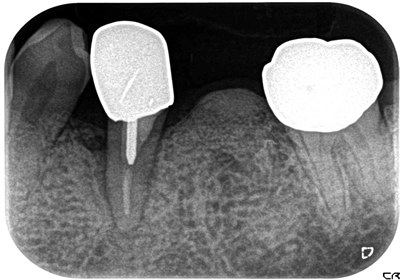

主訴 右下中切歯からの排膿により来院。

まずは、約1ヶ月のブラッシング指導、噛み合わせの調整、プラークコントールが15%以下になったのを確認。

その後、フラップオペ(歯肉を開く)をし、縁下歯石の除去、歯周組織再生剤のリグロスを注入し、縫合。

約25ヶ月経過後、骨の高さも確認でき、クリアに皮質骨もできてきている。

費用 8万 (オペ・歯周組織再生剤を含む)